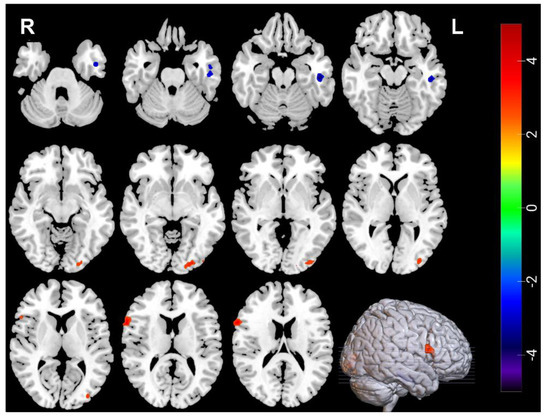

| Measures | Brain Regions | Voxel Size | Peak t Value | MNI Coordinates | ||

|---|---|---|---|---|---|---|

| Decreased | ||||||

| ALFF | Amygdala_R | 31 | −4.637 | 33 | 0 | −21 |

| ALFF | Temporal_Inf_L | 30 | −3.6166 | −51 | −24 | −18 |

| ReHo | Temporal_Inf_L | 45 | −4.3107 | −48 | −21 | −18 |

| Increased | ||||||

| ReHo | Frontal_Inf_Oper_R | 40 | 4.0503 | 63 | 15 | 15 |

| ReHo | Occipital_Mid_L | 41 | 3.7464 | −36 | −84 | 6 |